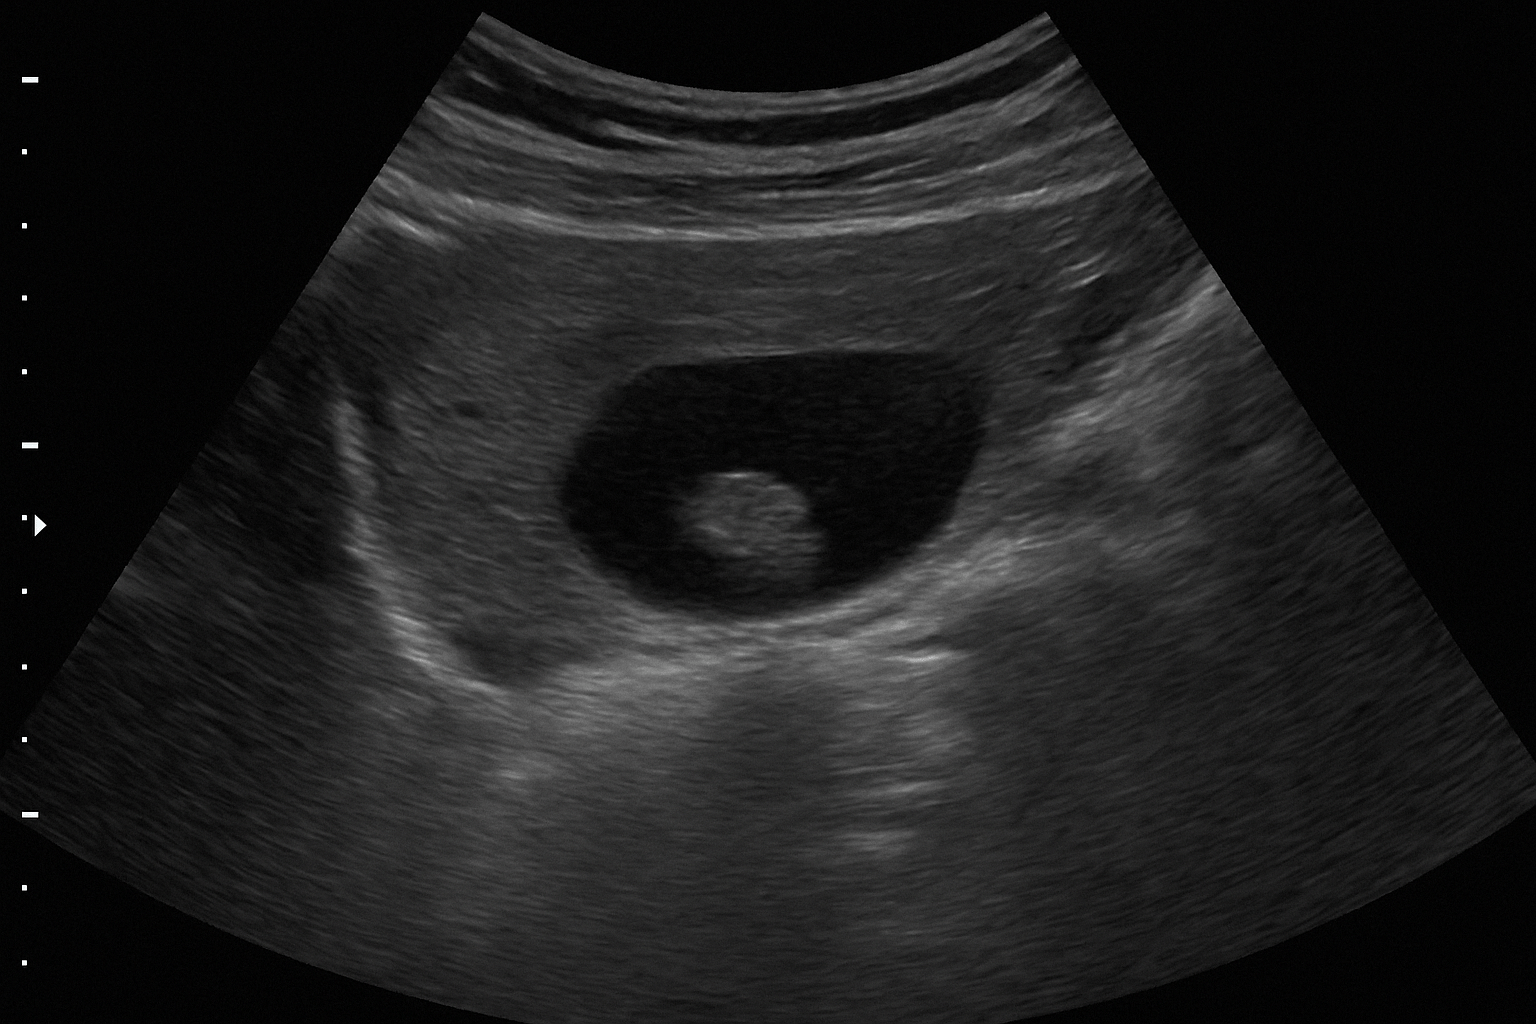

سونوگرافی از شن کلیه

سونوگرافی کلیه و مجاری ادراری یک روش غیرتهاجمی و رایج است که میتواند وجود رسوبات و انسداد احتمالی را نشان دهد. با این حال، دقت آن برای شنهای بسیار ریز محدود است. در موارد مشکوک، CT-Scan بدون کنتراست بهترین روش محسوب میشود، زیرا حتی کوچکترین کریستالها را نیز آشکار میکند.